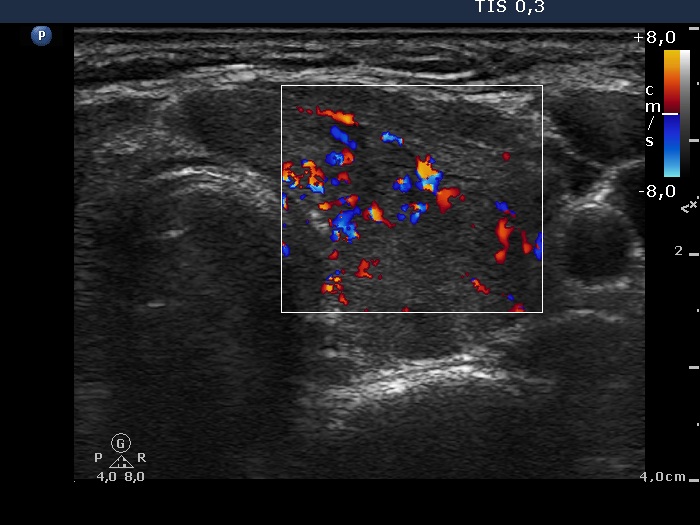

Chronic lymphocytic thyroiditis - Case 15. (ultrasonographic picture 5)

Left lobe, horizontal view. The vascularization is increased.